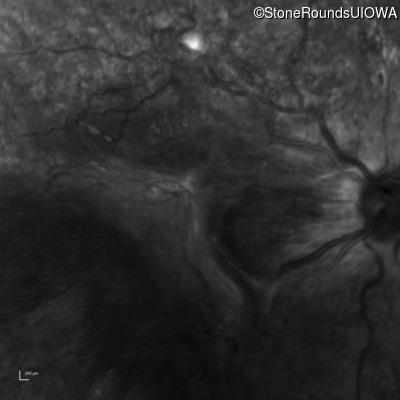

Infrared Fundus Photograph - Left - 20/250 sc

Exemplar